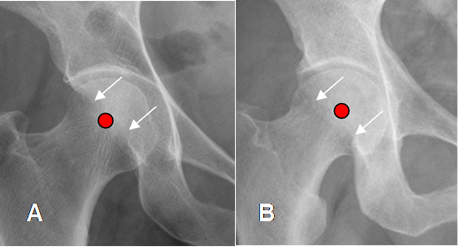

Signo de la pared posterior: El borde posterior del acetábulo, normalmente es medial al centro de la cabeza femoral. (4). Si lo sobrepasa, indica sobrecubrimiento posterior o retroversión acetabular. (4). (Fig 13).

Fig 13. Sobrecubrimiento posterior.

A: Rx AP. Borde acetabular posterior, medial al centro de la cabeza femoral.

B: Rx AP. El borde acetabular posterior es lateral al centro de la cabeza femoral, por sobrecubrimiento posterior.